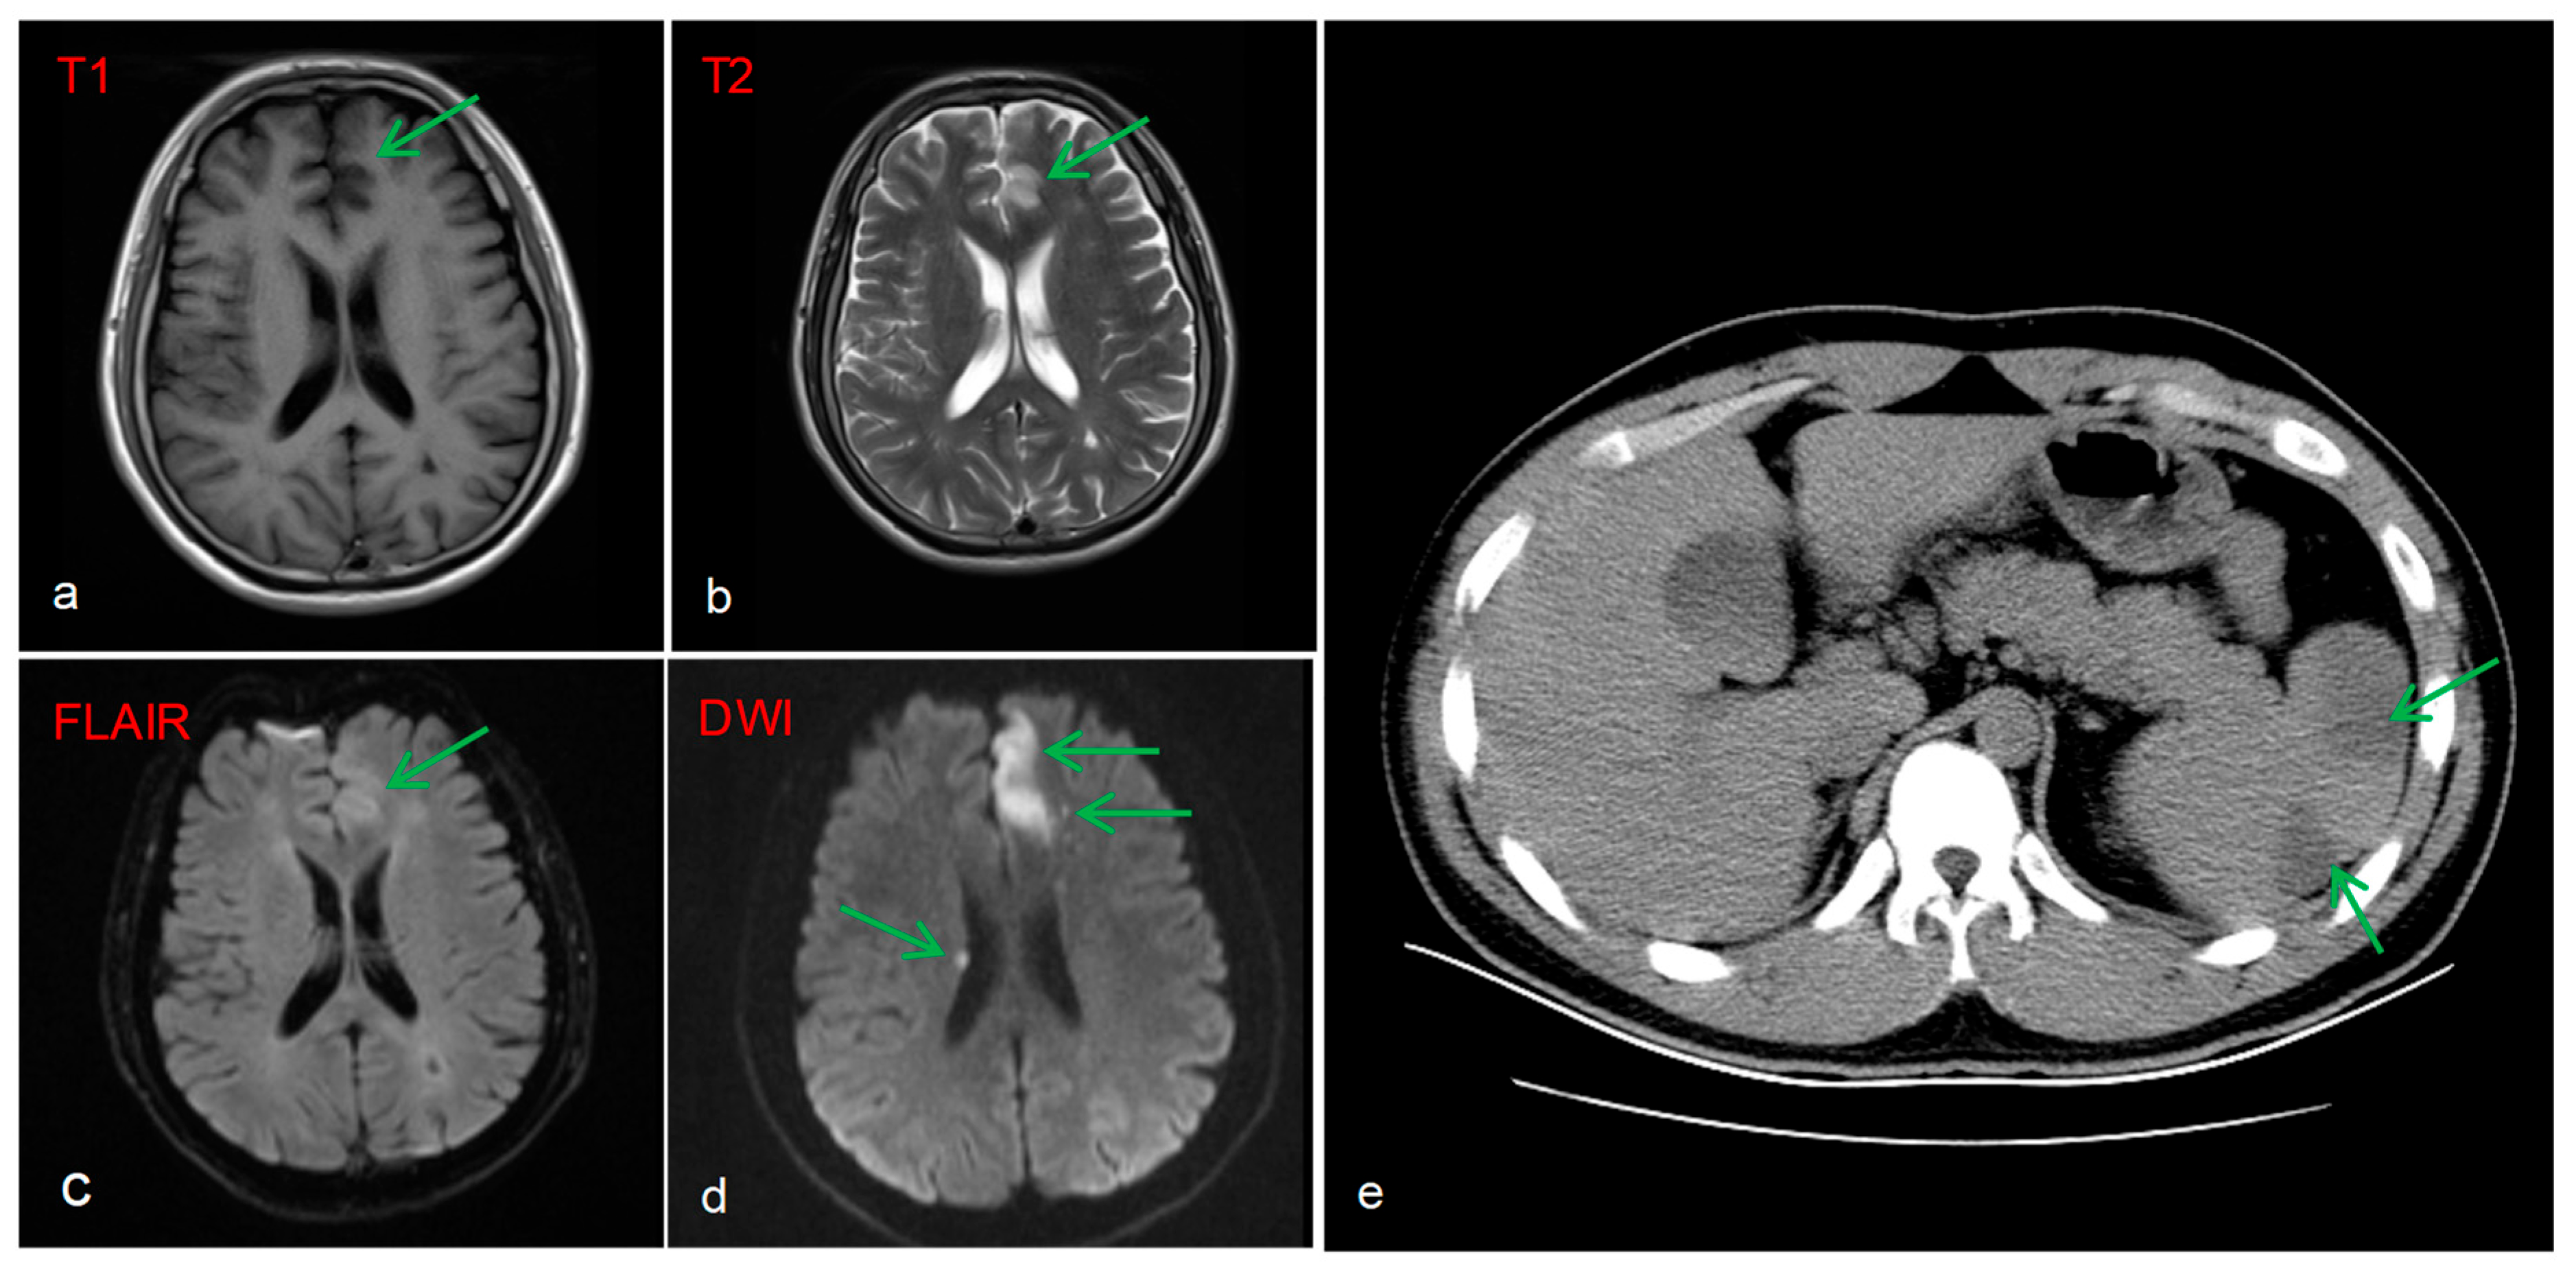

Brain MRI image revealed multiple acute infarcts (hyperintense on DWI) in the left fronto-parieto-occipital lobes, and periventricular regions, with the most prominent lesion in the left frontal lobe (Figure 3a–d). A protrusion in the A2 segment of the left anterior cerebral artery and a congenital variation of the right anterior cerebral artery were identified as potential anatomical substrates for stroke. Additionally, a CT scan of the abdomen showed splenomegaly with patchy hypodensities, consistent with splenic infarction (Figure 3e).

Figure 3. Brain MRI image: Fresh cerebral infarction in the left frontal lobe and right lateral periventricular region (ad). Abdominal CT: Radiolucent low-density lesion suggestive of splenic infarction (e).